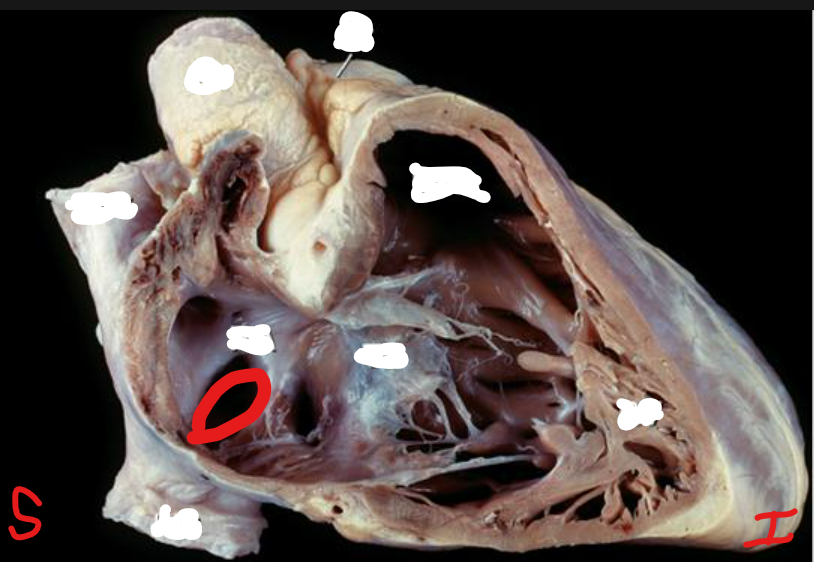

Q

Name this structure. What is the term for the structure it is on?

A

Fossa Ovalis

Interatrial Septum